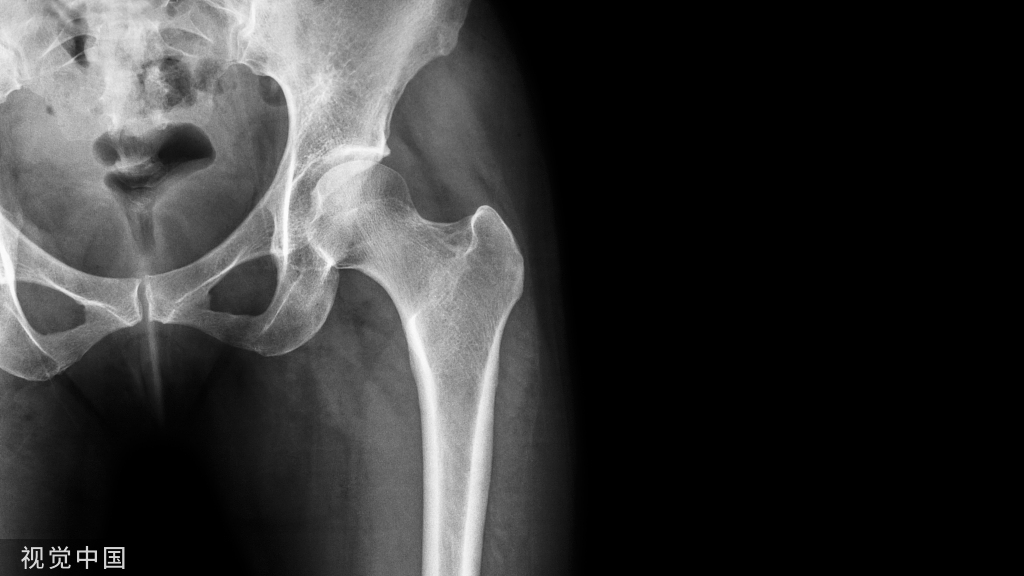

对于影像引导下的手术,了解腰椎动静脉血管及其在对侧入路结构至关重要。术前应仔细检查磁共振成像(MRI)和计算机断层扫描(CT)。应测量腰大肌前缘与腰前动脉(主动脉或左髂动脉)左外侧缘之间的距离。

有学者建议在该距离小于1cm时,应选择其他腰椎融合术,因为存在血管损伤以及腰大肌和腰丛的风险。另外,要考虑到可以通过腰大肌前腹部的轻微收缩获得的面积增加。

因此,我们不仅可以从CT/MRI图像中获得一个固定的OLIF通道,而且可以通过腰大肌的收缩来获得灵活的OLIF通道。

图示:术前测量手术通道。患者右侧卧位时L4–L5节段的CT轴位图。